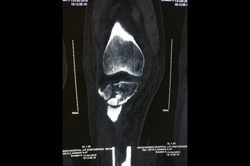

Arthroscopy - ACL Reconstruction, Maniscus Injury